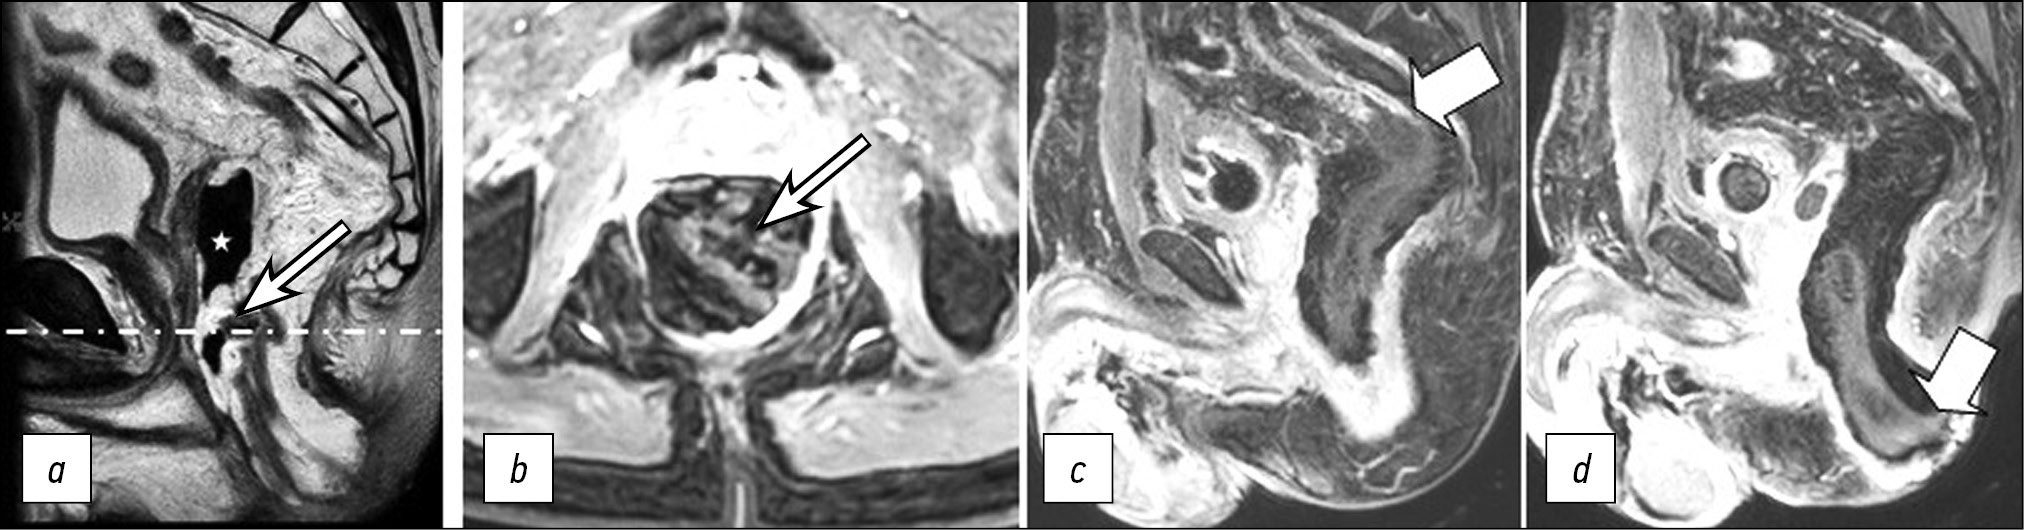

On the follow-up non-contrast-enhanced MRI, the previously detected changes (diffuse edema of the distal colon wall) were accompanied by a defect in the anterior wall of the coloplasty pouch, with a parietal air-filled cavity at the bottom in which a small amount of exudate was detected (Fig. 3). There were signs of necrosis in the pulled-through colon on rectoscopy (Fig. 4): the mucosa was violet-gray and dull; the lumen was deformed, and the folds were absent; the lumen contained blood and necrotic masses, and there was a putrid odor.

Figure 3. Pelvic MRI scans in Т2 mode on POD 6: two adjacent sagittal sections including the upper (a) and lower (b) segments of the pulled-through colon, with persistent diffuse edema of the walls; axial section (с) at the level of the dashed-dotted line. A defect in the anterior wall of the coloplasty pouch (arrow) with a parietal air-filled cavity (asterisk).

Necrosis of the pulled-through colon segment, which necessitates emergency surgery, is an unfavorable outcome of acute ischemia. In our case, a follow-up MRI (POD 6) revealed diffuse edema in the pulled-through colon segment wall that persisted and an area of tissue destruction appeared. A defect containing fluid and gas formed in the wall of the coloplasty pouch. Changes in the MRI pattern were detected on POD 10 despite ongoing conservative therapy. A follow-up endoscopic examination confirmed the MRI findings of necrotic changes. Additionally, signs of a general inflammatory response increased, necessitating relaparotomy with disconnection of the anastomosis and resection of the necrotic portion of the colon.